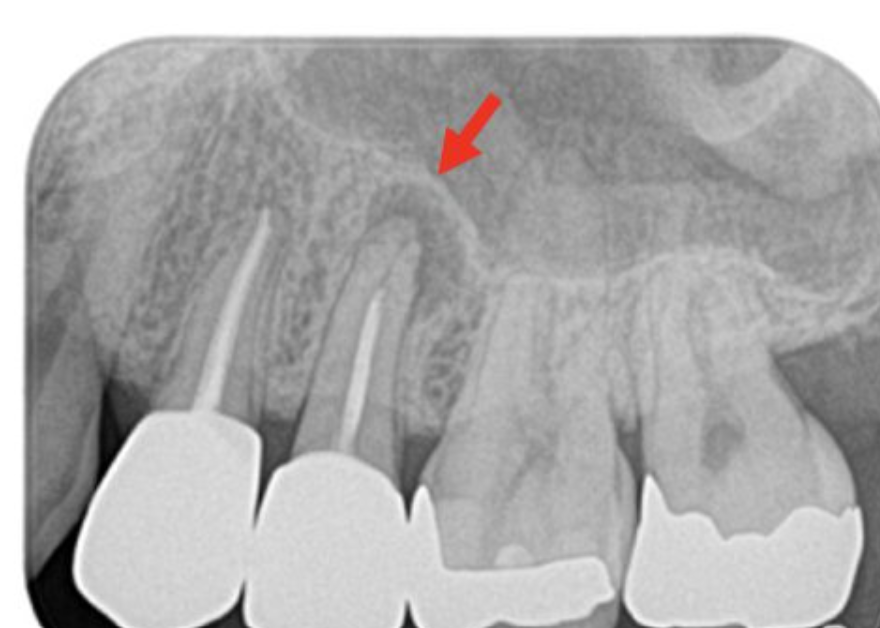

歯の違和感の原因のひとつに、歯の根の先にできた膿の袋や炎症があります。

これを放置すると、顔の骨(歯槽骨)がじわじわと溶けてしまうことも。

「根尖性歯周炎(こんせんせいししゅうえん)」などと呼ばれ、

自覚症状がないまま進行してしまうケースも少なくありません。

実は、通常のレントゲンでは角度的にうまく映らなかったり、病変が小さすぎて確認できないこともあるのです。

そういった場合、違和感や痛みといった症状をきっかけにCTを撮影したことで、初めて問題が発見されるというケースは珍しくありません。

CTは立体的に撮影できるため、通常のレントゲンでは見えにくい部分も明確に把握できます。